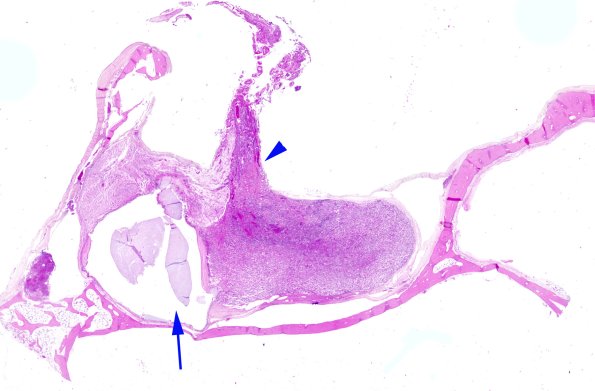

1A The pituitary in situ. The arrowhead designates the stalk and the arrow demonstrates a small Rathke’s cleft cyst between the adenohypophysis and neurohypophysis. (H&E)